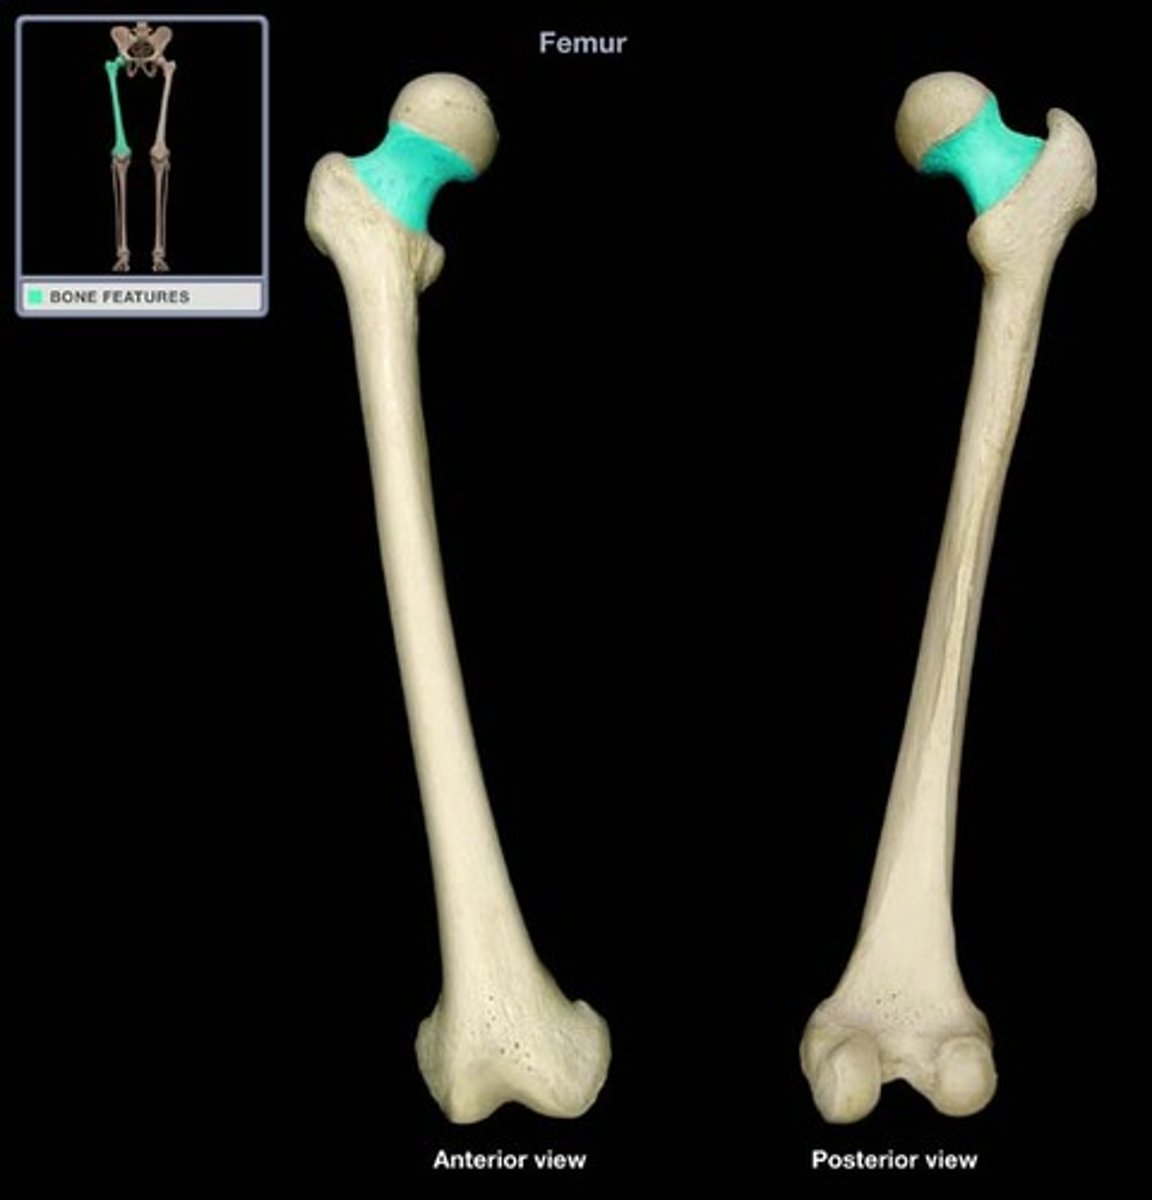

Femur

Head of the Femur

Neck of the Femur